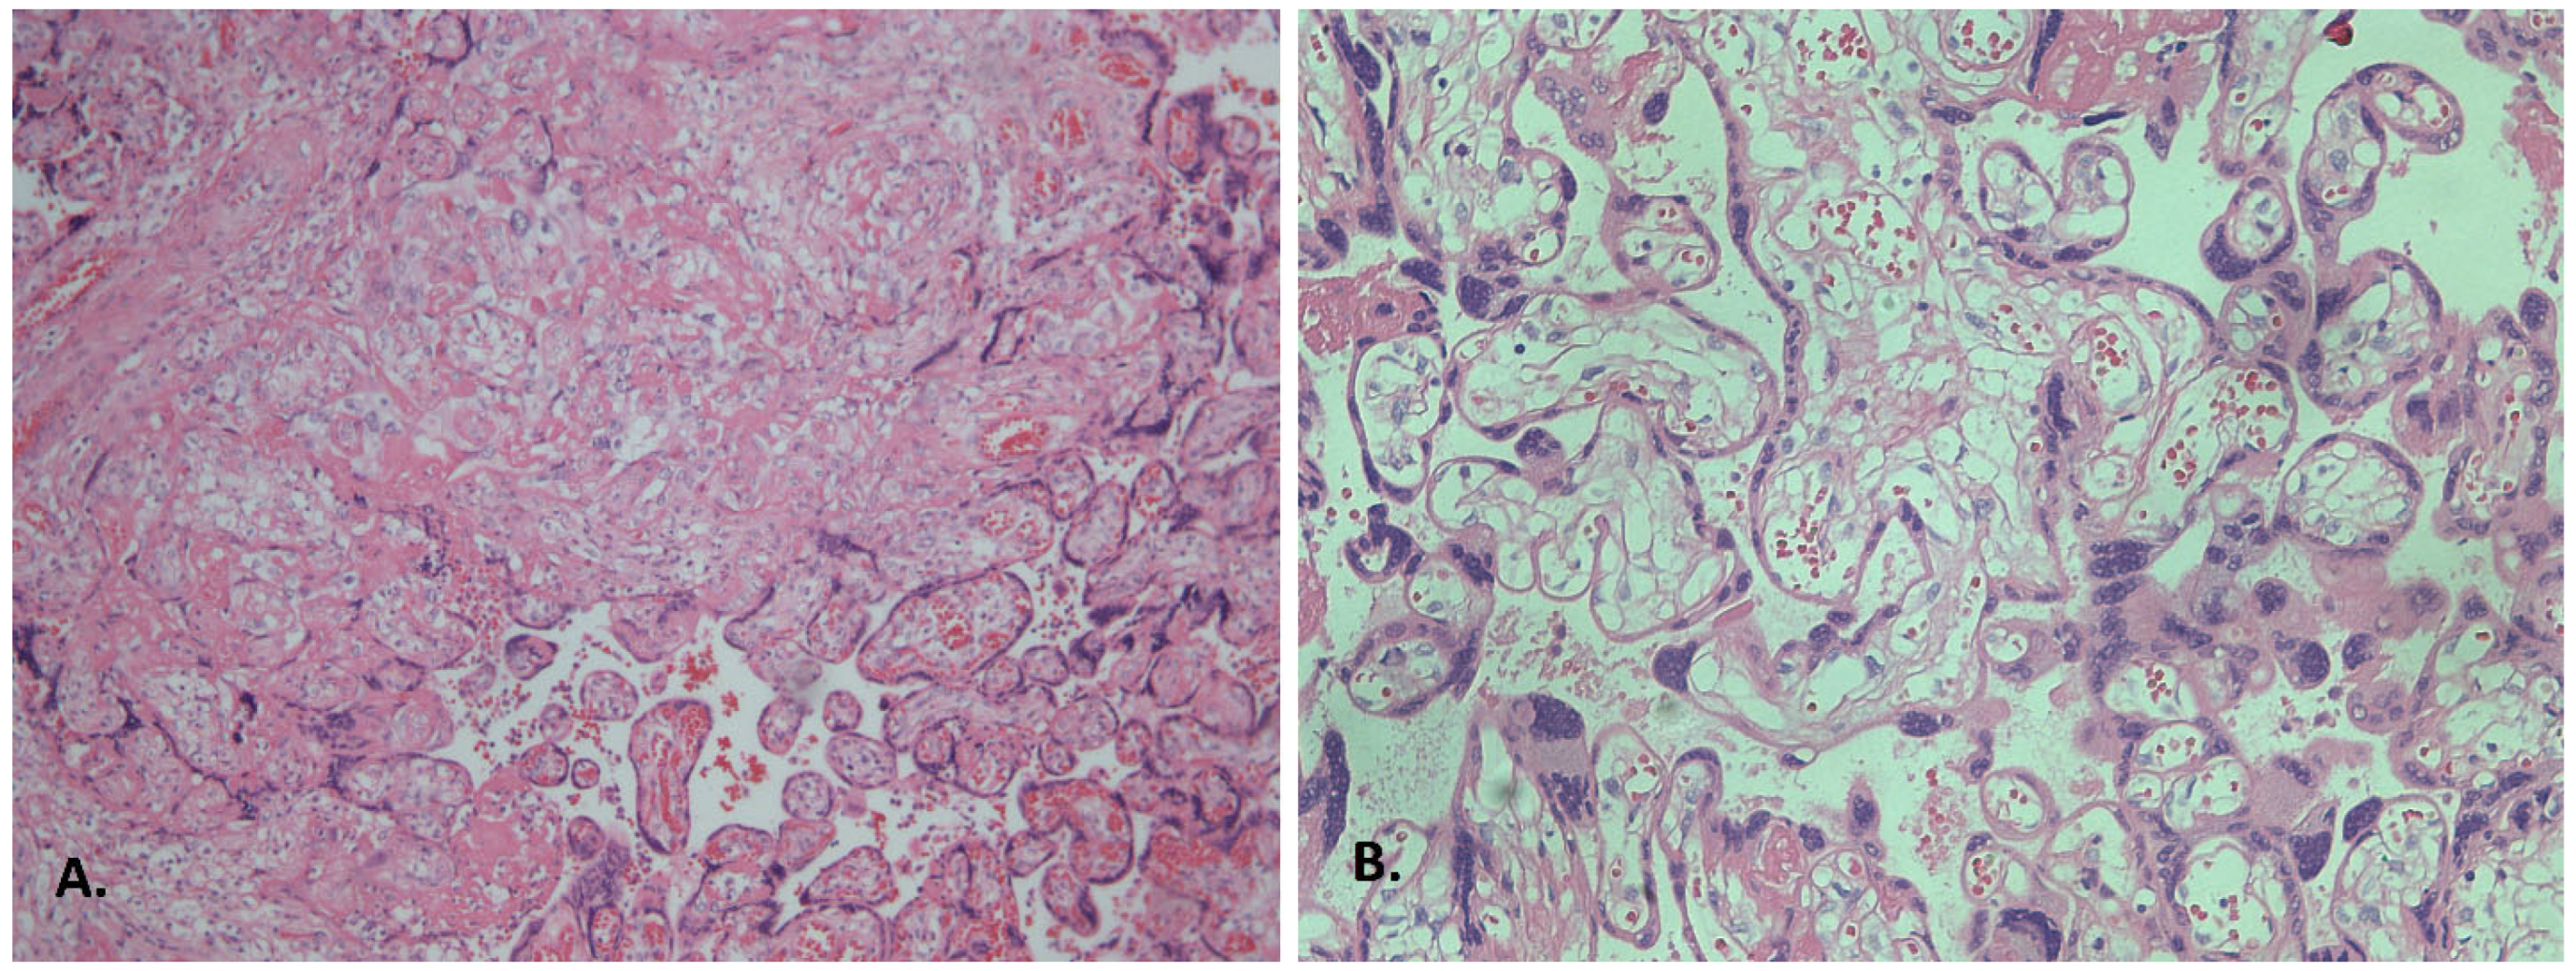

3.2. Histological Findings

3.2.1. Inflammatory Alterations